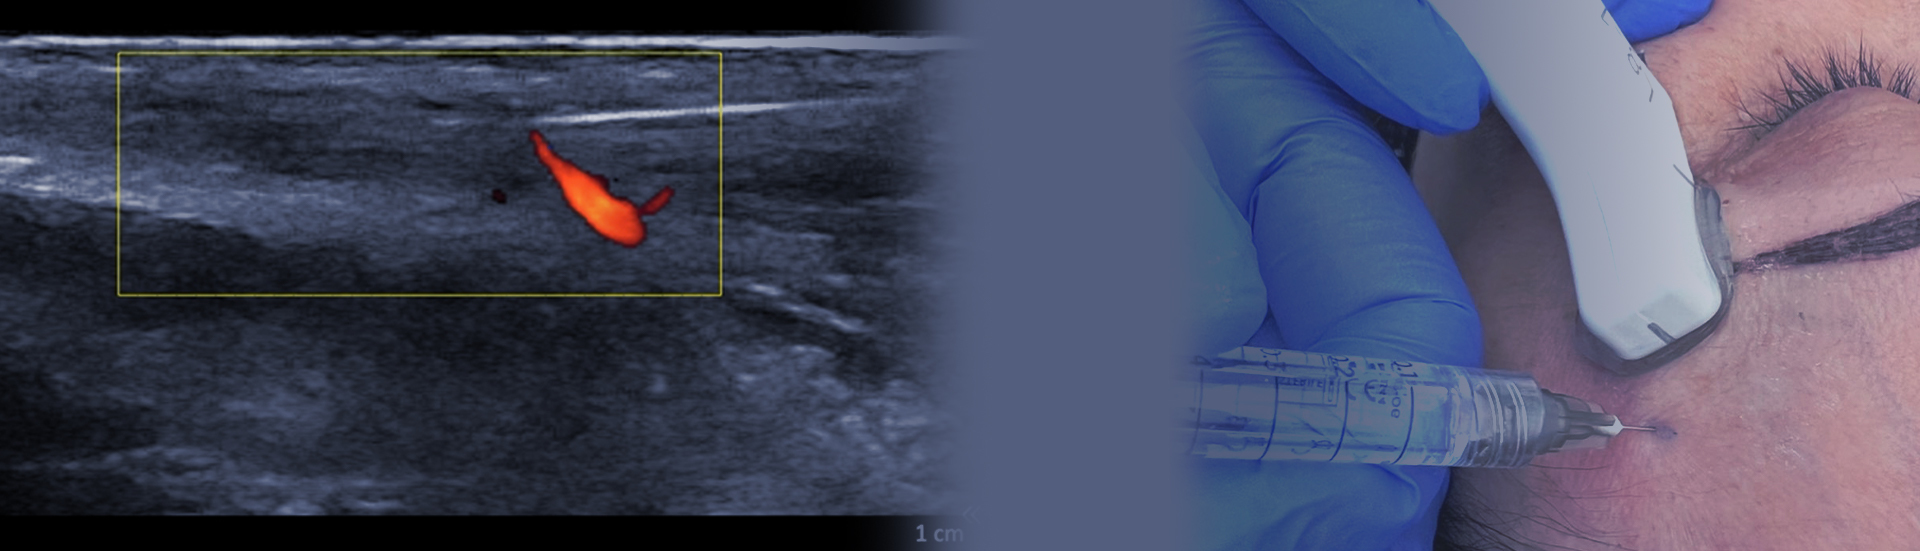

The sonography is a dynamic image method and allows the injector to visualize facial structures during the procedure, identify the best injection plan and avoid important vascular structures. It also allows to differentiate previously injected fillers and guide the treatments of complications.

• Teach you the basic technique to perform ultrasound guided injections